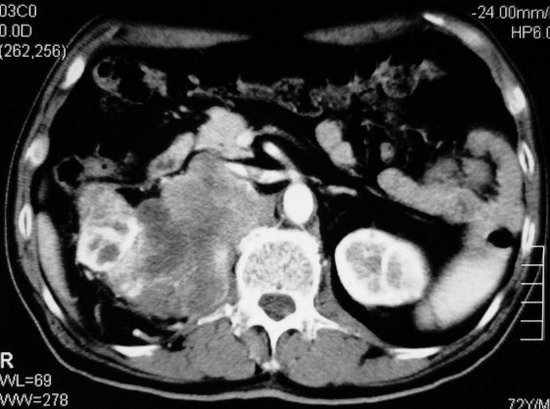

以下是引用杀毒软件在2008-11-17 19:15:00的发言:[br]考虑------右肾癌合并肾静脉---同侧肾上腺受侵可能性大

以下是引用zjzjr在2008-11-17 20:45:00的发言:[br]考虑------右肾癌合并肾静脉---同侧肾上腺受侵可能性大及腹膜后淋巴结转移.